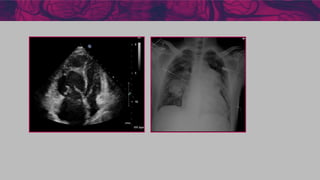

Imagem (ECO /

cardioRNM)

Área AD < 18 cm2

Sem derrame

pericárdico

Área AD 18-26 cm2

Sem ou mínimo derrame

Área AD > 26 cm2

Derrame